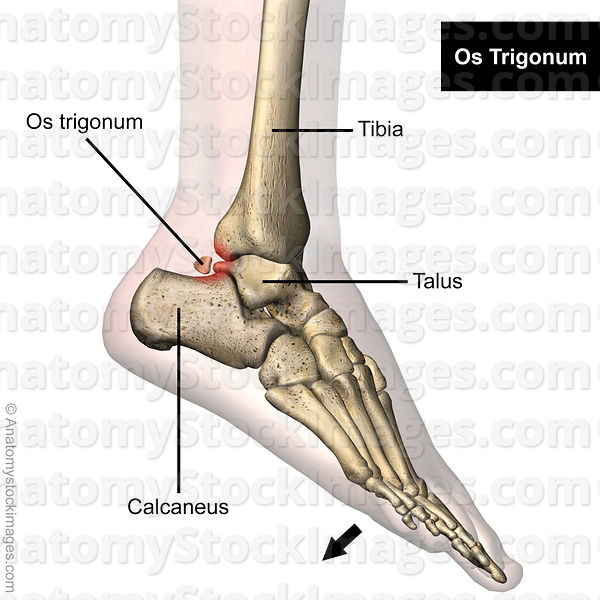

大多数后撞击综合征与距骨后方相关。距骨后外侧的继发骨化中心在8-13岁左右形成,随后在1年内融合。偶尔(约7%),可能与形成的距后三角骨不融合。此外,这个骨化中心可能仍然突出所谓的“Stieda's突(距骨后突)”(图11)。

除距骨后外侧外,韧带解剖包括(从上到下):(1)距骨后下韧带,从外踝延伸至胫骨后外侧;(2)胫腓横韧带,从腓骨延伸至胫骨后、内踝;(3) 胫骨slip,也称为后踝间韧带,起源于胫骨后部,插入距腓后韧带;和(4)距骨后韧带从外踝延伸至距骨后外侧(图11)。

(1)急性足底过度屈曲损伤和(2)慢性重复性微创伤。这两种机制的相似之处在于后部软组织,后者可能在距骨后和跟骨之间继发性肥大和压缩。骨体的存在(距后三角骨(OT)和Stieda突)会进一步缩小这个空间,这导致了它的另一个名称“距后三角骨综合征”(图12)。51这种增生的压迫导致区域肌腱和韧带的损伤。拇长屈肌腱鞘炎通常受累(图12)。重要的细分包括跟腱肌病/撕裂、关节病、急性距骨后突骨折、拇长屈肌腱鞘炎、Haglund综合征、骨软骨损伤和跟骨后滑囊炎。

图12。

后踝关节撞击的侧位矢状位图示:(a)足底弯曲的踝关节伴有相关的os三角,后软组织被卡压,包括距骨后韧带(PTFL)和相关的滑膜炎。(b) 由于两者关系密切,刺激和增厚的屈肌支持带可引起长屈肌肌腱刺激和腱鞘炎。